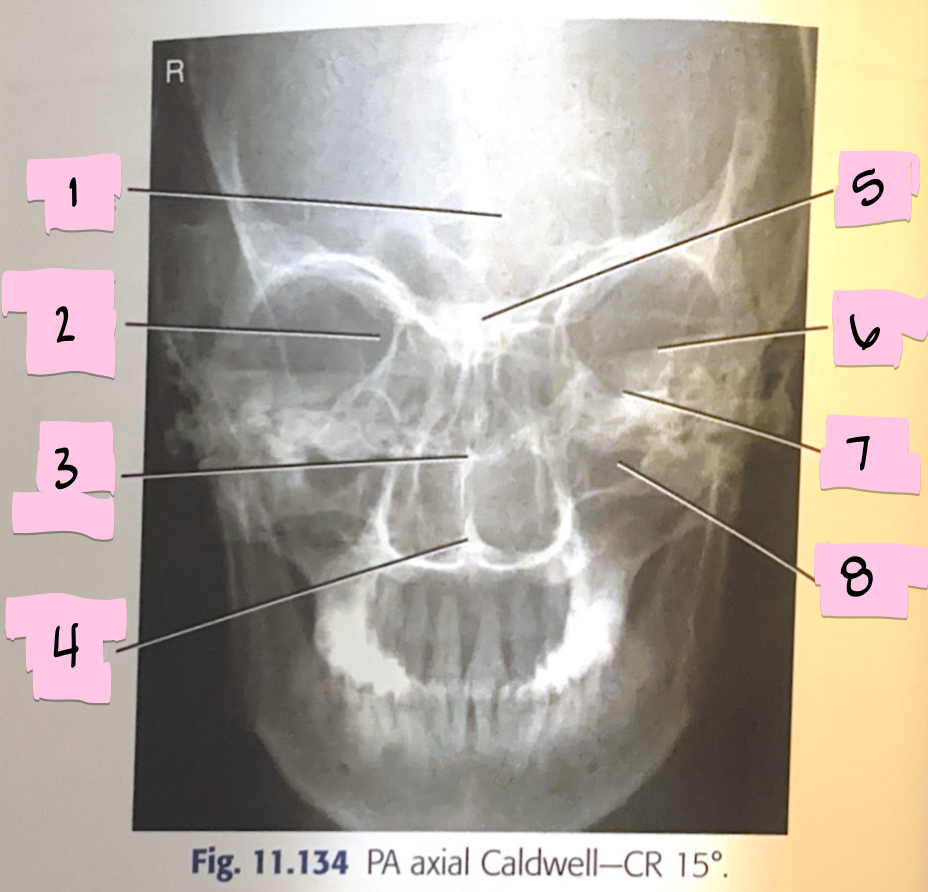

What is 1 pointing to?

Frontal sinus

What is 2 pointing to?

Superior orbital fissure

What is 3 pointing to?

Bony nasal septum

What is 4 pointing to?

Anterior nasal spine

What is 5 pointing to?

Crista galli

What is 6 pointing to?

Petrous ridge

What is 7 pointing to?

Floor of orbit

What is 8 pointing to?

Maxillary sinus